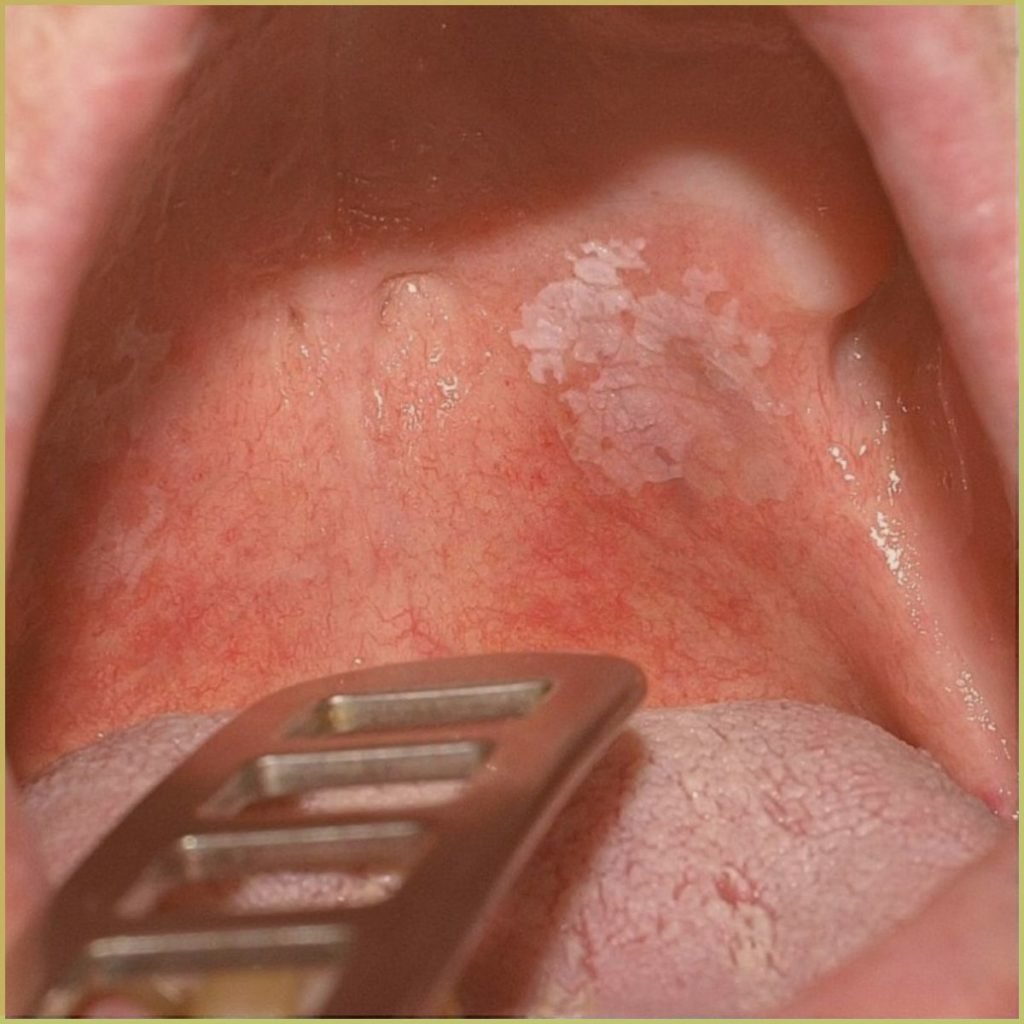

HAIRY LEUKOPLAKIA

Hairy leukoplakia is a distinct inflammatory reaction of the tongue strongly associated with an Epstein-Barr virus infection. It is most often seen in patients who are immunocompromised (e.g. AIDS) and could be a herald for an undiagnosed systemic condition. The common clinical presentation includes:

- A characteristic corrugated or shaggy appearance on the lateral border of the tongue.

- Early lesion – fine white vertical streaks.

- Mature lesion – may be thickened to be plaque-like.

- Extensive lesions may involve the dorsum of tongue and buccal mucosa.

Diagnosis is based on the lesion history, clinical presentation and microscopic findings, which may include characteristic EBV nuclear inclusions within the superficial keratinocytes. Your differential diagnosis should include:

- Frictional hyperkeratosis.

- Lichen planus.

- Hyperplastic candidiasis.

Treatment is not necessary, but antiviral therapies (acyclovir) may be appropriate to improve aesthetics.